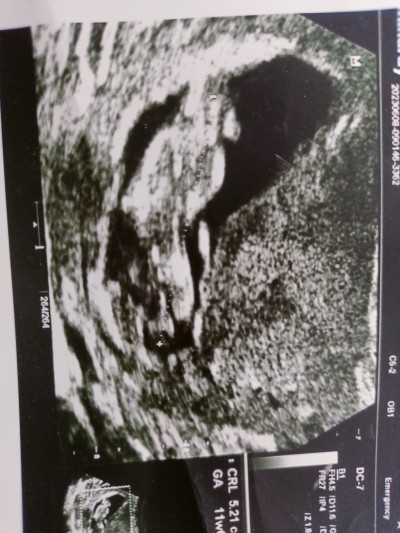

13 haftalık karından ultrason. Tahminde bulunabilen varsa yardımcı olabilir mi?

Gebelik haftası 13